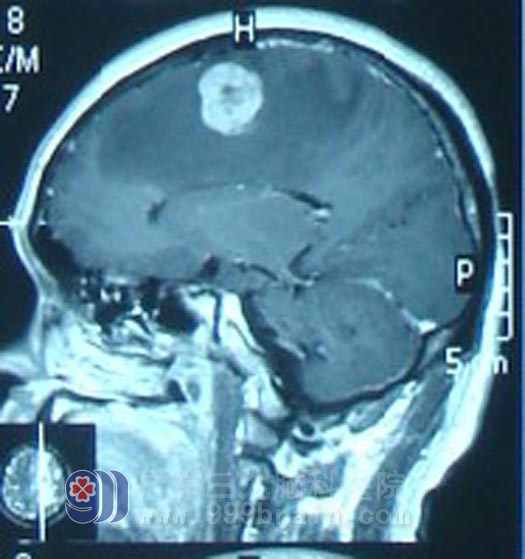

广东开平的梁先生,42岁,2010年12月开摩托车时突然晕厥,当即摔倒在地,不省人事,20分钟后意识清醒,在当地医院行头颅CT示左额顶叶多发占位。第二天即到广东三九脑科医院治疗。入院行头部MR检查示左额顶叶多发占位性病变,胸部X线示右肺下野中内带肿块影,考虑肿瘤性病变。虽然梁先生无其他躯体症状,但结合其影像检查结果考虑为肺癌脑转移。

完善相关检查后,梁先生接受了左额中央区转移瘤切除术,术后病理回报是高至中分化腺癌。梁先生术后今年1月开始行全脑放疗及肺部适形放疗,后脑局部再行X刀加量治疗。放疗期间,梁先生未出现特殊不适。放疗结束后遵嘱按时行6周期静脉化疗。现梁先生一般情况良好,复查MR显示肿瘤明显缩小,得到了良好的控制。http://www.999brain.com/

头部放疗前